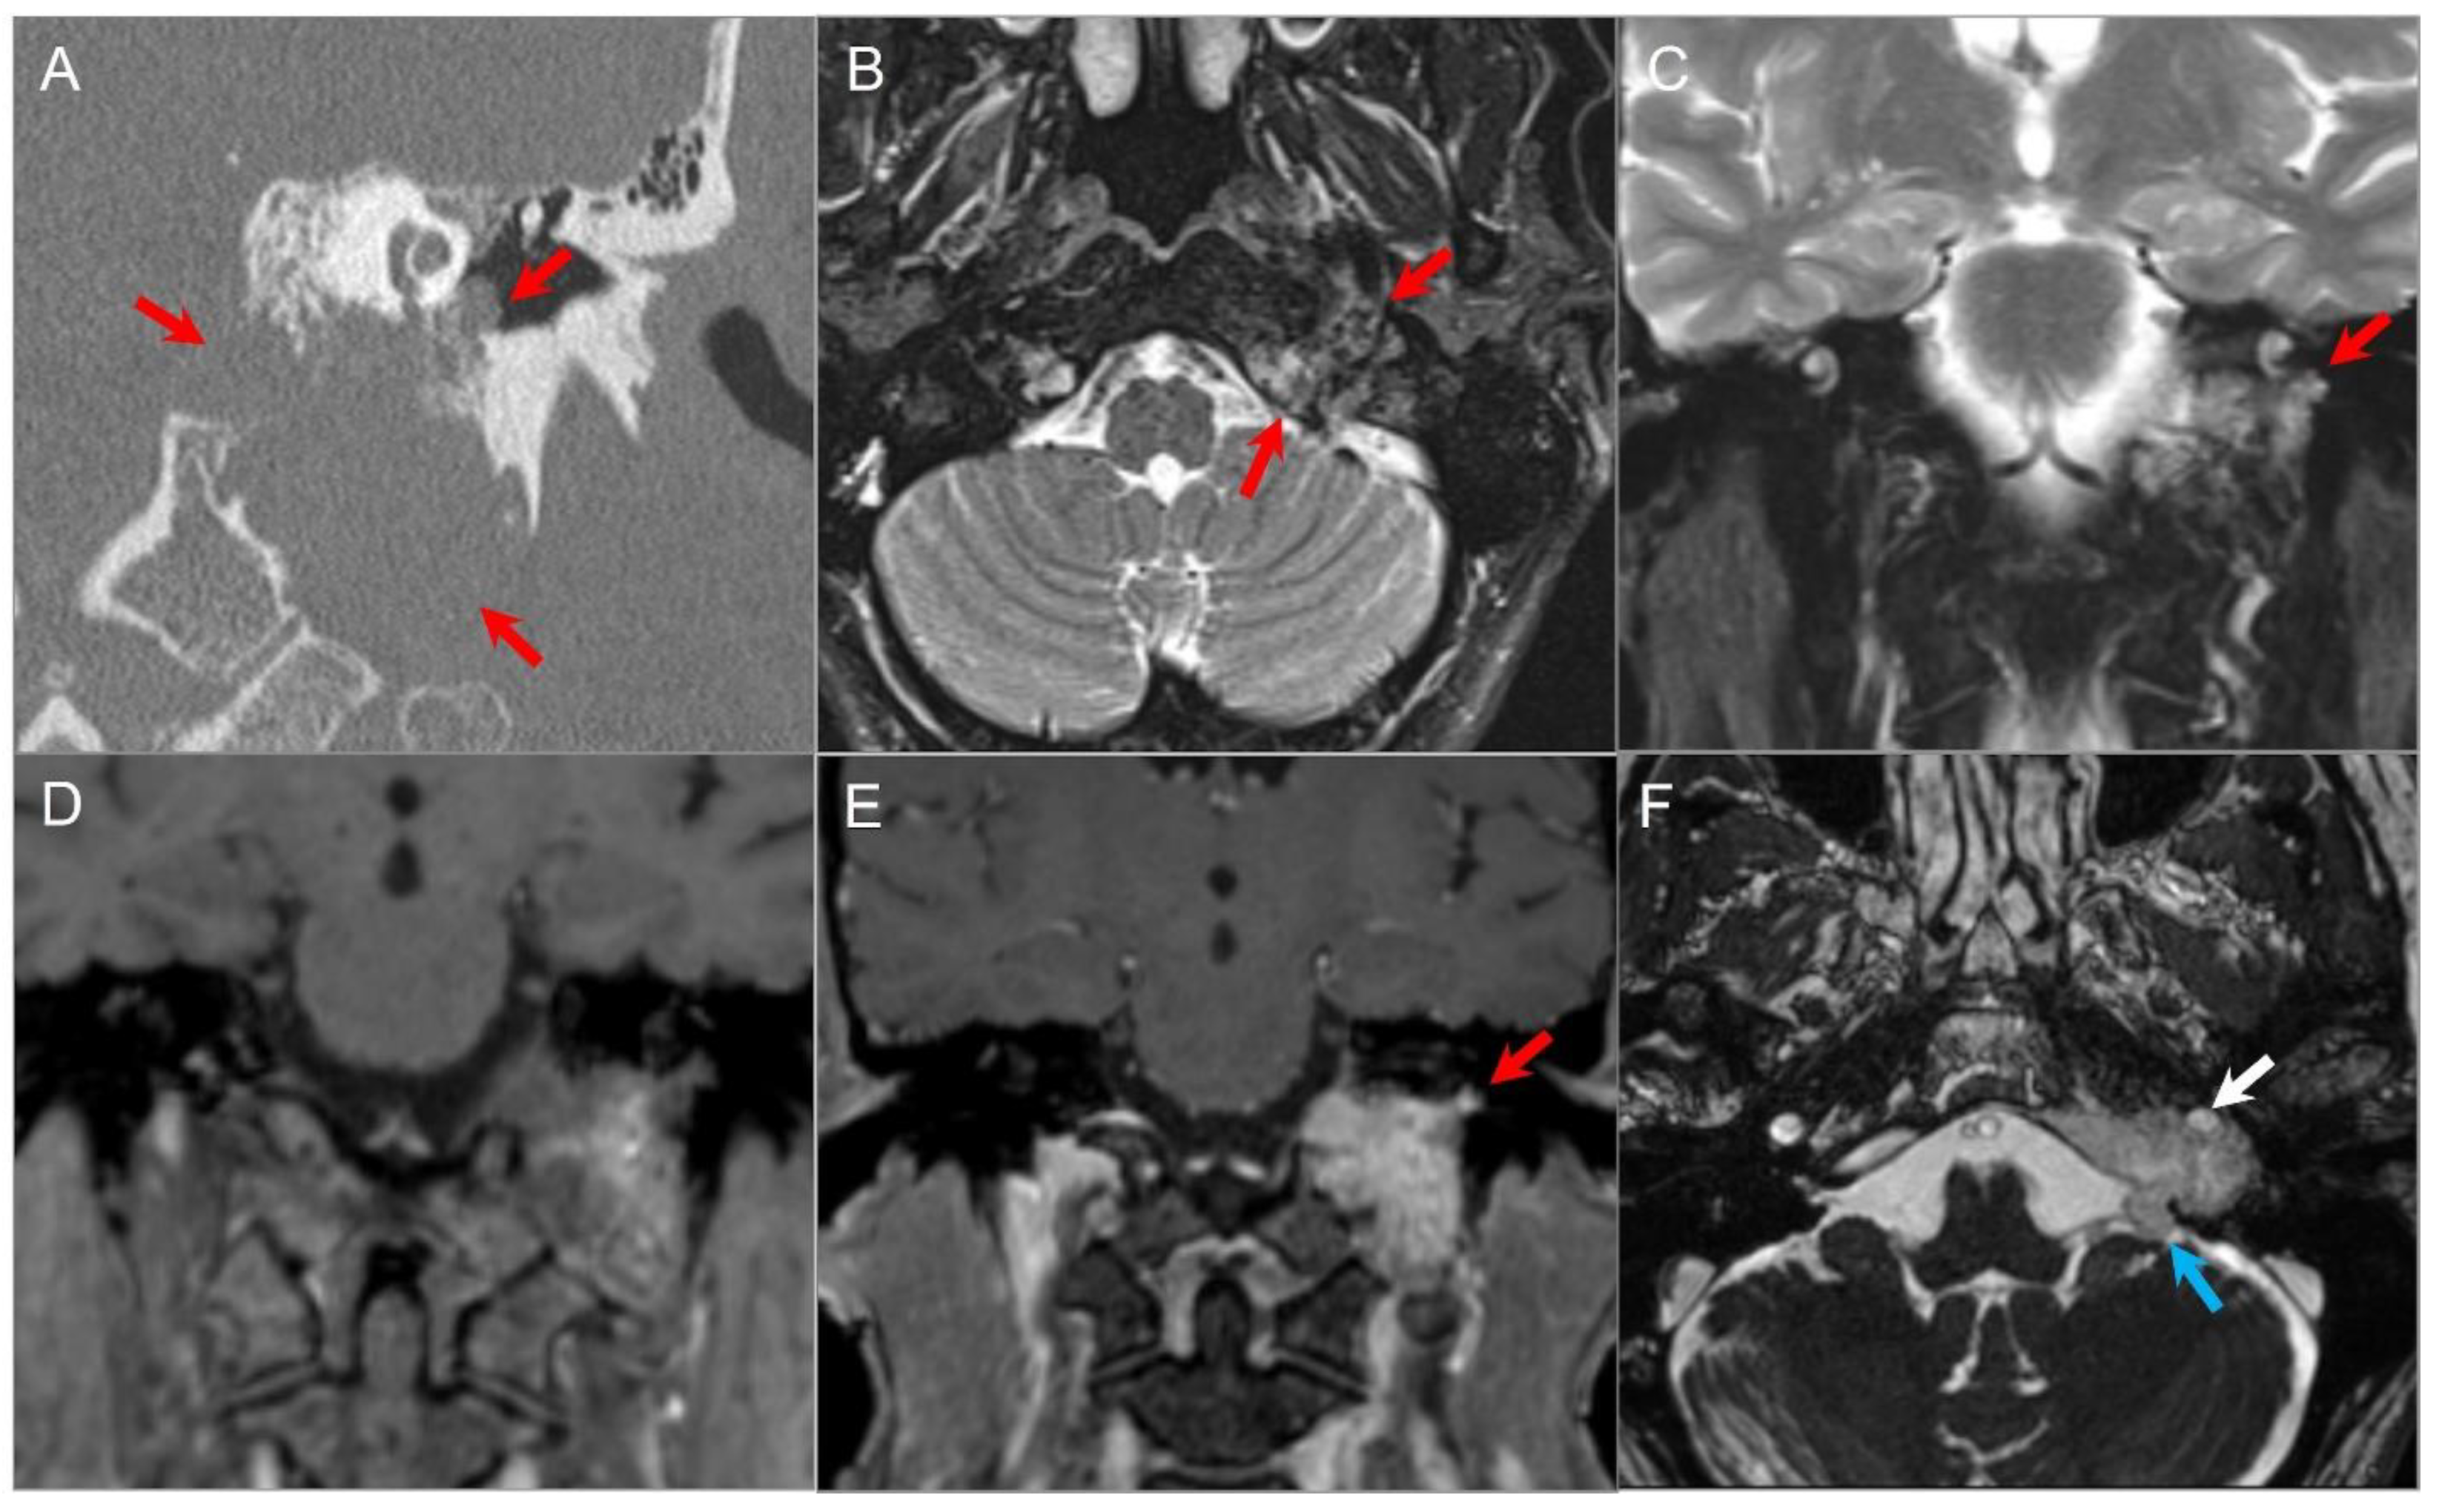

4.4.4. Endolymphatic Sac Tumor